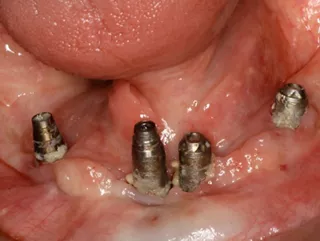

Seguida de la colocación inmediata de 4 implantes Straumann TLC™, ∅ 3,75 mm x 10 mm (44, 42, 32), ∅ 3,75 mm x 12 mm (34) SLActive®, Roxolid® y restauración provisional inmediata.